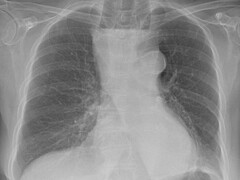

Beeldquiz

Stel je diagnose op basis van een foto. De wekelijkse beeldquiz van het NTVG is een leuke manier om je kennis snel te testen en te vergelijken met anderen.